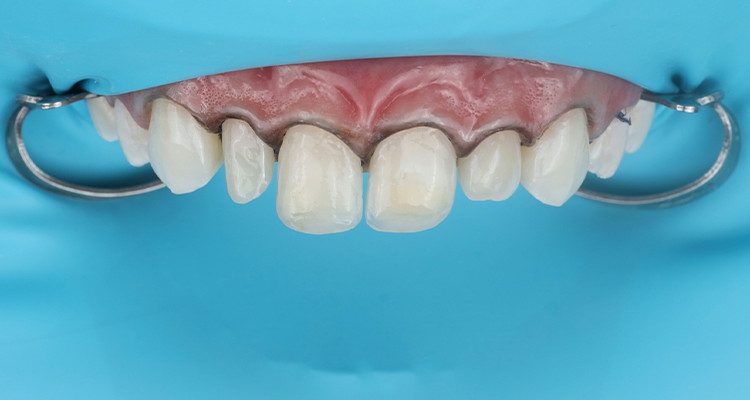

3 | Condicionamento ácido total de superfície com Condac 37, com isolamento absoluto modificado e fios retratores posicionados.